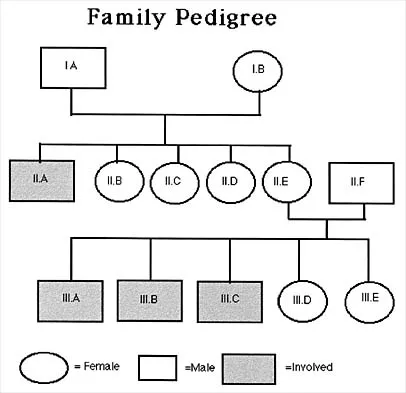

Figure 53 shows the pedigree of a family with an unusual type of muscular dystrophy. This pedigree is most consistent with what type of inheritance pattern?

Explanation